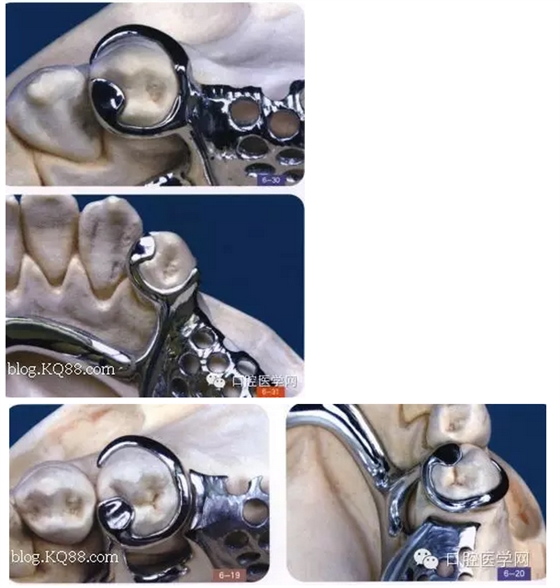

其實(shí)RPI,RPA卡換組對(duì)于后牙游離缺失在臨床中很常用,CPI卡換組由三部分組成,近中和支托,遠(yuǎn)中臨面板,和頰側(cè)I桿組成,近中和支托起一個(gè)應(yīng)力中斷作用,能有效預(yù)防近中基牙扭轉(zhuǎn)

1是近中合支托,2是臨面板,3是I桿

CPI卡環(huán)應(yīng)用于遠(yuǎn)中游離缺失,近中基牙不健康的基牙,當(dāng)遠(yuǎn)中產(chǎn)生一個(gè)向黏膜處的壓力時(shí),把力量通過近中和支托,傳寄給基牙,而不是直接在遠(yuǎn)中處直接傳給給基牙,這樣就產(chǎn)生了一個(gè)應(yīng)力中斷作用能有效保護(hù)基牙,同時(shí)頰側(cè)和遠(yuǎn)中的I桿和臨面板下沉,滑動(dòng),能有效預(yù)防基牙扭轉(zhuǎn),同時(shí)I型卡環(huán)與基牙的接觸面積比較小能防止食物存留預(yù)防繼發(fā)齲但是有一前提:游離缺失處,牙槽脊條件比較好,對(duì)于牙槽脊條件差者,要設(shè)計(jì)遠(yuǎn)中合支托,如果頰側(cè)牙體倒凹大,口腔前庭小于5mm者要設(shè)計(jì)CPA卡換組(以下圖片來自中醫(yī)大)

(CPA及變異CPA卡環(huán)組)